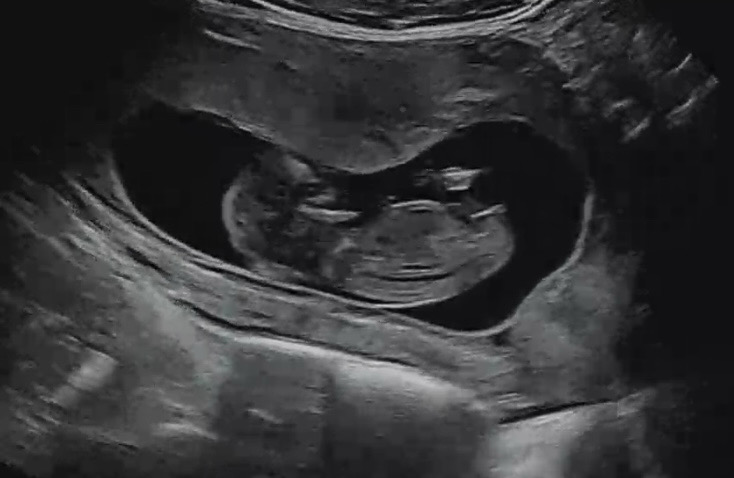

12주5일차 각도법 봐주실 분 있으신가요🥹

12주5일차 각도법 투표 부탁드려요 ㅎㅎ